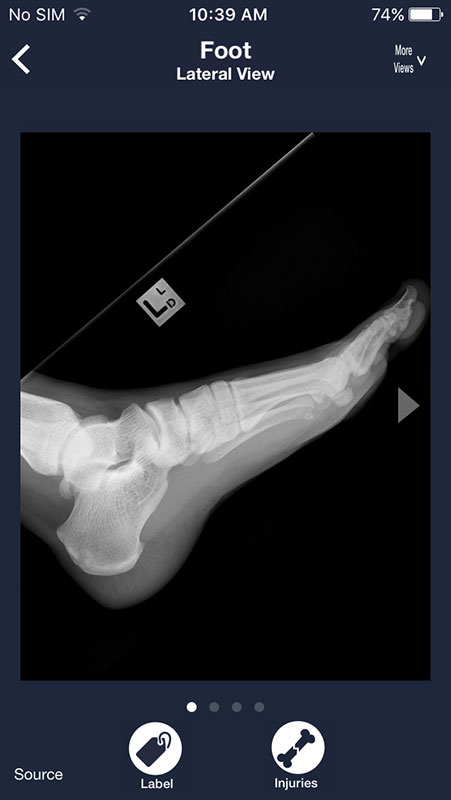

Most radiographs can be viewed from multiple angles. Simply tap on More Views above each image and choose between different views.

For example, you can view shoulder from AP view, apical oblique, or lateral Y, or choose to view chest X-rays from frontal or lateral view, which may be particularly useful to spot some abnormalities that might not be visible from frontal view (for example atelectasis).